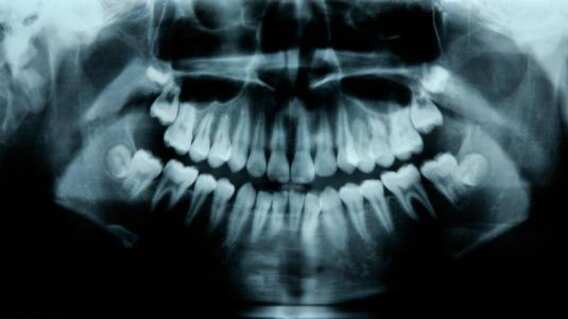

Según informa el New India Express, los facultativos ordenaron una radiografía y una tomografía computarizada para buscar el problema que padecía el menor, descubriendo que este tenía 526 dientes.

«El crecimiento similar a un tumor impidió el crecimiento permanente de los molares del lado afectado. La radiografía y la tomografía computarizada mostraron múltiples dientes rudimentarios en un tejido similar a una bolsa», manifestó.

«Los dientes eran de diferentes tamaños que variaban entre 0.1 mm y 15 mm. Parecían perlas en una ostra. Incluso la pieza más pequeña tenía una corona, raíz y una capa de esmalte como un diente», sostuvo Senthilnathan.